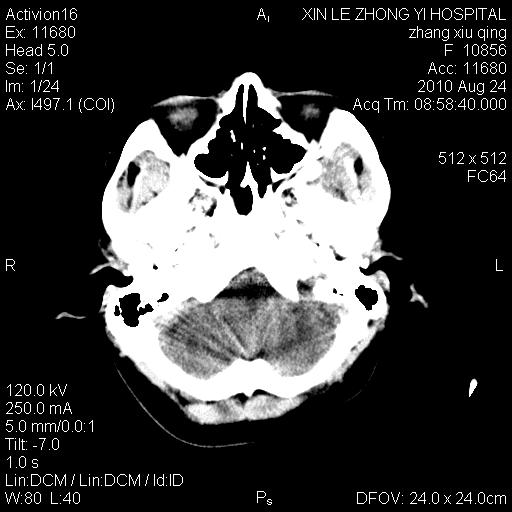

标题: CT28569:看看鞍上池正常吗

女 24 偶有头晕

怎么这么多伪影?我感觉没什么特别异常哦,是不是伪影所至呀

伪影多,建议行mri!